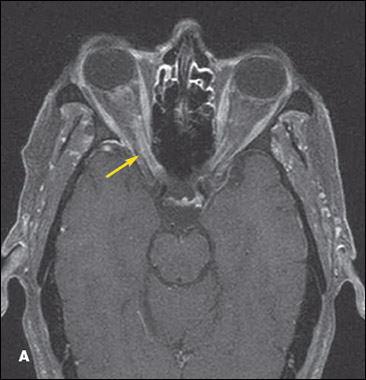

Findings on a CT scan of the head are unremarkable. MRI scans of the brain with gadolinium reveal enhancement along the meningeal surfaces of the right optic nerve and to a lesser degree of the left optic nerve (A), and expanded cranial nerves VII and VIII bilaterally (B). No evidence of hydrocephalus, intraparenchymal mass, or stroke is present.